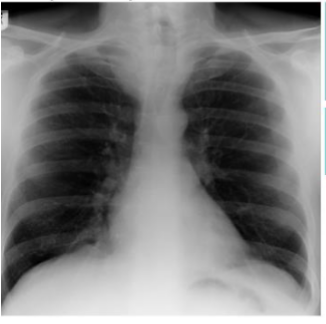

Label this CXR (10 things)

1) trachea 2) hilum- should have R and L 3) lungs 4) diaphragm 5) heart 6) aortic knuckle 7) ribs 8) scapulae 9) breasts 10) bowel gas